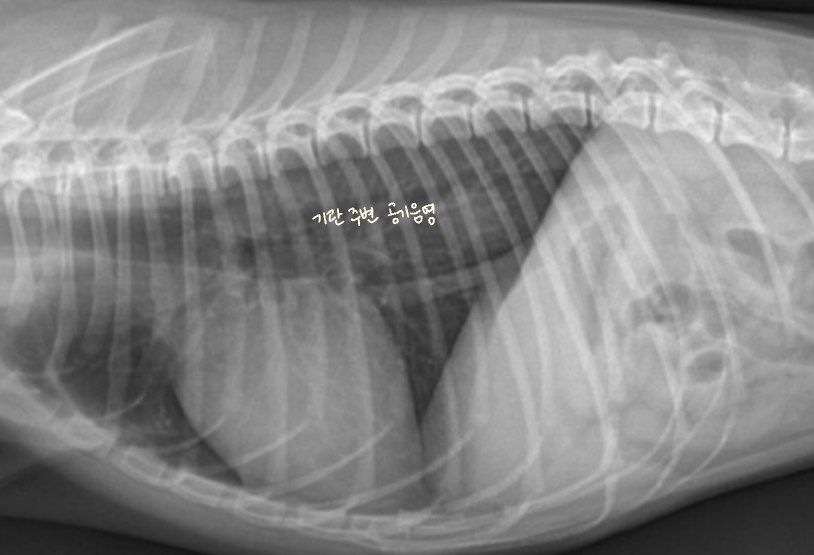

Tracheoesophageal strip sign (์๋ ๋ด ๊ฐ์ค ์ถ์ )

- Tracheoesophageal strip sign : ์๋ ํ์ฅ์ ์ํด ๊ธฐ๊ด๊ณผ ์๋๊ฐ ๊ฒน์ณ ๋ํ๋๋ ๊ฐ๋๊ณ ํํํ ๊ณต๊ธฐ ์์.

- ์๋์ ๊ฐ์ค ์ถ์ ๋์ด ์๋ค๋ฉด

- ํฅ๋ถ์ด๋ ๋ง์ทจ๋ก ์ธํ ์ผ์์ ์ถ์ (์ ์)

- ์ด๋ฌผ๋ก ์ธํ ๋งํ

- MG์ ์ํ ์๋ํ์ฅ์ฆ (์๋๊ทผ ๋ฌด๋ ฅํ)

| ์ ์ | Strip sign |